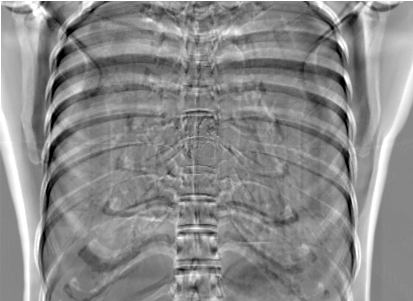

5.4 Real Knee Data with Metal Implants

Refer to caption

Figure 13: Three examples of synthetic perspective projection images for training, intensity window: [0, 4]. The appearance (e.g., image contrast and metal image resolution) of such DRR training images is different from that of real projection images in Fig. 14.

The complementary view setting for learning perspective deformation is also evaluated on real CBCT projection data. In this evaluation, real CBCT projection data from a dataset of knees with metal implants is used for testing, while DRRs created from volumetric CT datasets with inserted metals is used for training. Three exemplary DRR perspective projection images for training are displayed in Fig. 13, in which synthetic metal implants are inserted [34]. The appearance, e.g., image contrast and metal image resolution, of such DRR training images is different from that of real projection images in Fig. 14. In Fig. 14, the results for three knees, with and without metal implants, are displayed. The first and second rows are the 0superscript00^{\circ} and 180superscript180180^{\circ} perspective projections, respectively, rebinned to the virtual detector with geometric calibration based on their respective principal points and projections of the world origin. The third row displays their difference images, where the magnitude of deviation increases from the center towards the outside like it does in DRRs with an ideal scan trajectory (e.g., Fig. 6(e)), although real projection data suffer from various physical effects like beam hardening and Poisson noise. The fourth row displays the RGB stacks of 0superscript00^{\circ} and 180superscript180180^{\circ} perspective projection images. The magenta and green regions indicate structures with considerable perspective deformation, for example, the knee patella in Fig. 5.4, the top parts of the two metals in Fig. 5.4, and the bottom two screws in Fig. 5.4. The fifth row displays reference images, which are orthogonal projections of iterative reconstruction volumes from measured CBCT projection data. In the reference images, a total of five landmarks are selected, with the positions being marked by the green dots: In Fig. 5.4, two positions at the edges of the knee patella are marked; In Fig. 14(e) and Fig. 14(f), one position at the left edge of the fibula is marked for each image. In addition, a rectangular frame for the two metals is marked by the green dashed lines, while its width and height are indicated by the green solid lines, which are 29.71 mm and 111.99 mm, respectively. In Fig. 14(f), the centerlines of the bottom two screws are sketched by the green lines, which have the lengths of 17.14 mm (middle screw) and 19.38 mm (bottom screw). The corresponding rectangular frame for the two metals and the screw centerlines in the perspective projection images are marked as well, but in red color. In Fig. 14(a), the width and height of the metals are 32.56 mm and 109.85 mm, which have deviations of 2.84 mm and -1.95 mm to the reference ones, respectively. In Fig. 14(b), the centerline lengths are 18.91 mm and 19.54 mm, which have deviations of 1.77 mm and 0.16 mm, respectively. Although the bottom screw has little length deviation to the reference, the orientations of both screws are obviously deviated. The sixth row shows the results of Pix2pixGAN using 0superscript00^{\circ} and 180superscript180180^{\circ} polar inputs. For all of the landmarks, the green reference dots are all located accurately in the Pix2pixGAN images. The rectangular reference frame also accurately covers the metals in Fig. 14(g). In Fig. 14(h), although the two red centerlines do not exactly overlap with the green one, they are very close in lengths and orientations. Please zoom in for better visualization.

The region-of-interest covering the cavity/fracture structures indicated by the red arrow in Fig. 14 has been enlarged in Fig. 15 for better visualization of image resolution. In the real 0superscript00^{\circ} perspective projection ROI (Fig. 15(a)), the cavities and bone edges appear sharp. The presence of Poisson noise can also be visualized to some degree. In the DRR reference ROI (Fig. 15(b)), the cavities and bone edges appear blurry. This is likely caused by the partial volume effect in the intermediate 3D reconstruction volumes. In the Pix2pixGAN output (Fig. 15(c)), there is a slight smoothing effect. For example, the fine edge indicated by the arrow is blurred and the Poisson noise is reduced. But in general, image resolution is preserved for most anatomical structures, e.g., the cavities.